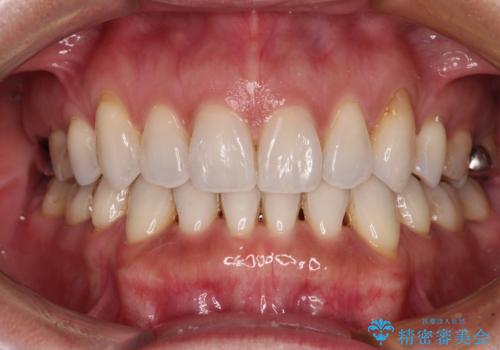

動きにくい歯はやはり動きにくく、咬み合わせ改善に時間を要しましたが、患者様には大変満足していただけました。